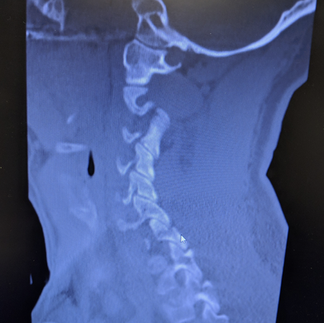

It's actually my husband's story, but I had to witness the pain and recovery associated with his mountain bike crash 5 years ago. Luckily, I had just bought him a new helmet, complete with MIPS by Troy Lee Designs, about 6 months prior to this bike accident. I am 100% convinced this helmet saved him from a brain injury as the force of the impact on his head was enough to cause a fracture through the posterior part of his C6 vertebrae. Although he was lucky to escape this crash without any concussion symptoms, and without a spinal cord injury, the fracture and associated nerve injury was still a lot of manage. Luckily the neurosurgeon did a great job and Kris healed very well from a C6-7 anterior fusion and is able to bike again without any issues!